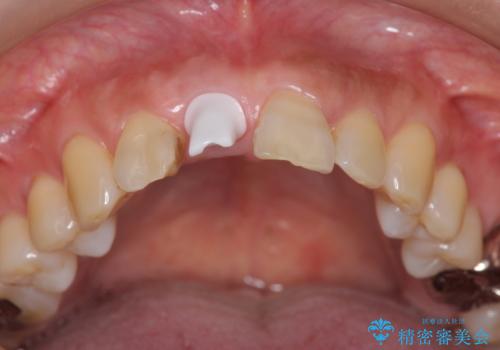

- 目立つ一番前の歯を失い、接着剤で応急処置をしていましたが永続性のある修復を希望され来院されました。

入れ歯・ブリッジ・インプラントによる欠損補綴の方法のうち審美的で取り外しがなく隣の歯を削らない治療を望まれたため、インプラントによる審美・機能回復治療を計画します。

前歯のインプラント治療は適切に行えば、ブリッジのように隣の歯を削らずに審美的で機能的な状態に仕上げることが可能です。

インプラント周囲に十分な骨や歯ぐきの厚みの整備を行うことで、審美的なインプラントの仕上がりを達成することができます。